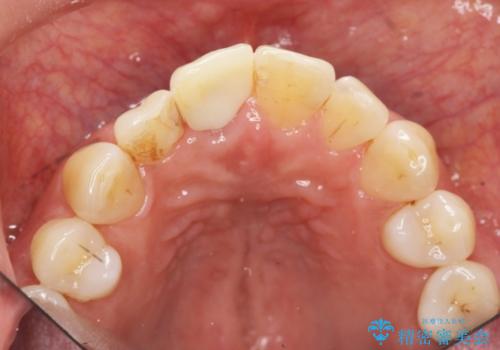

前歯 インプラントによる欠損補綴

前歯のインプラント治療は適切に行えば、ブリッジのように隣の歯を削らずに審美的で機能的な状態に仕上げることが可能です。

インプラント周囲に十分な骨や歯ぐきの厚みの整備を行うことで、審美的なインプラントの仕上がりを達成することができます。